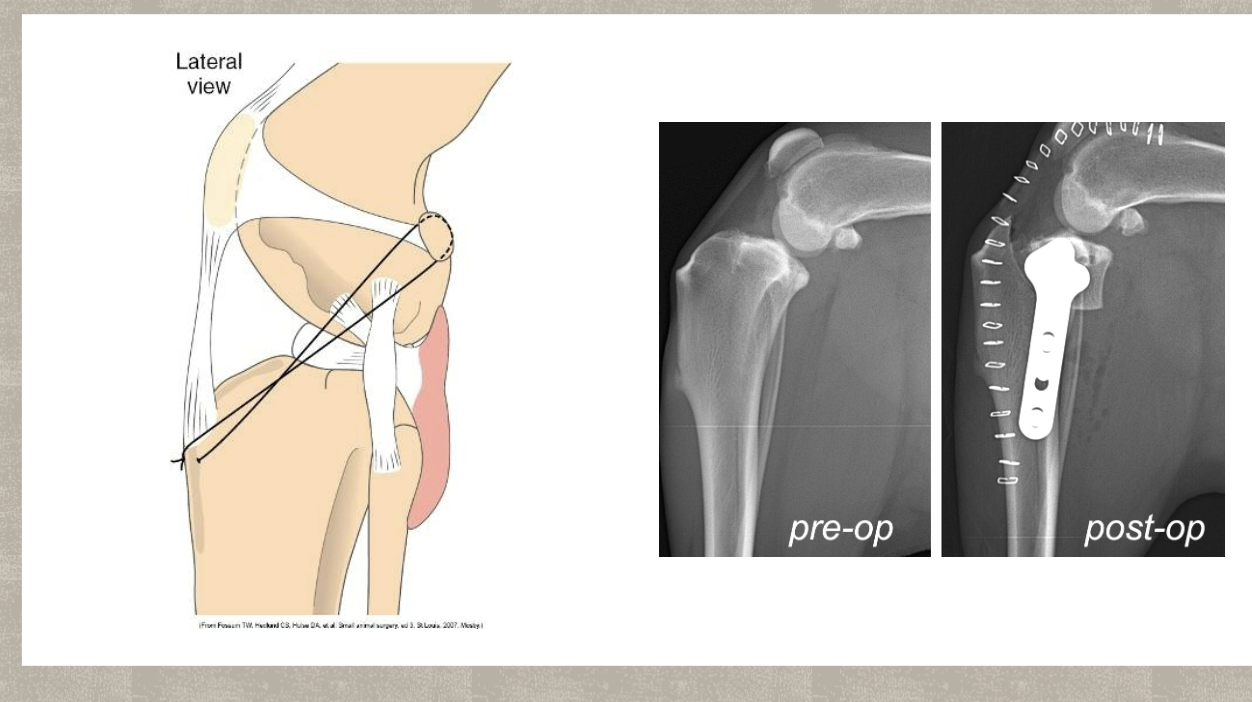

CCL treatment Surgical repair

Is considered the gold standard

Intracapsular

extracapsular

TPLO